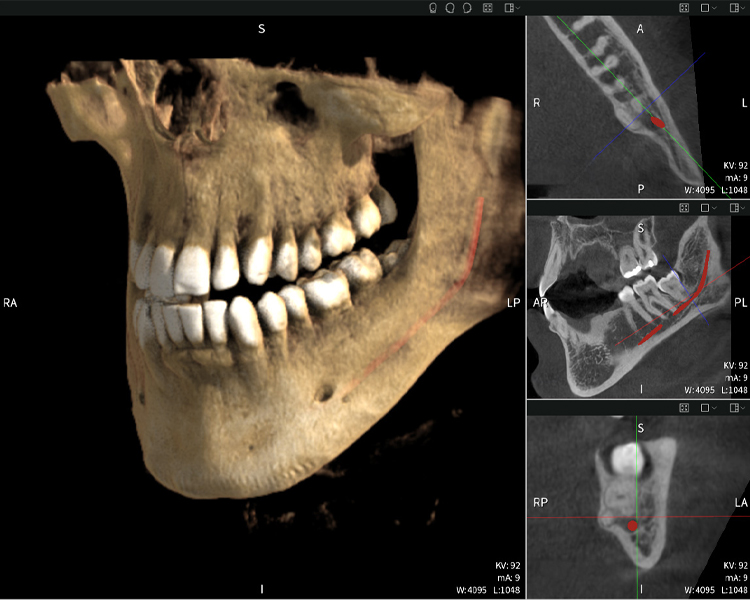

A continuación encontrarás un caso del Dr. med. dent. Oliver A. Centrella, en el cual las imágenes CBCT obtenidas con Seethrough Max proporcionaron información crucial sobre la anatomía compleja y la relación crítica entre las muelas del juicio y el nervio alveolar inferior. En este caso, existe una indicación para la extracción quirúrgica de las muelas del juicio.

Figura a: Resultados de imagen de Seethrough Max, sobre un fondo negro.

Figura a

• Arriba a la izquierda: Corte axial de la mandíbula izquierda (región 38) que muestra el nervio alveolar inferior (en rojo) en proximidad a las raíces del diente 38.

• Arriba a la derecha: Reconstrucción 3D de toda la mandíbula para orientación. El nervio alveolar inferior marcado en rojo ilustra su ubicación dentro del hueso mandibular.

• Abajo a la izquierda: Vista sagital de la mandíbula (región 38), destacando la estrecha relación espacial entre las raíces y el conducto del nervio.

• Abajo a la derecha: Vista coronal de la mandíbula (región 38), crucial para evaluar la posición espacial de las raíces en relación con el nervio.